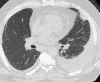

In the era of Precision Medicine, diagnostic imaging plays a key role in initial diagnosis and treatment response assessment in thoracic manifestation of various rheumatic disorders; resulting in increased dependency on imaging for treatment planning. Chest radiographs serve as a good initial screening tool for assessment of emergent and urgent thoracic conditions, e.g., pneumothorax, pulmonary edema, consolidation and pleural effusions. Cross-sectional imaging techniques, e.g., computed tomography (CT) and positron emission tomography-computed tomography (PET-CT) are most commonly utilized to evaluate more detailed pulmonary and mediastinal manifestations of rheumatic conditions. Magnetic resonance imaging (MRI) and ultrasound are most commonly used in cardiovascular, neural and musculoskeletal structures. This review article aims to highly key common thoracic imaging findings of rheumatic disorders, highlighting imaging test of choice for the particular disorder.